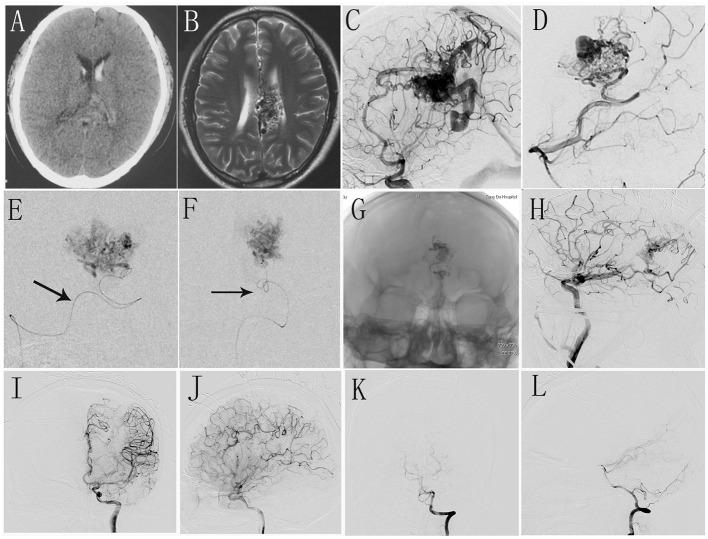

一站式杂交手术治疗脑动静脉畸形的围手术期疗效及安全性:单中心初步经验

Peri-procedure efficacy and safety of one-stop hybrid surgery for the treatment of brain arteriovenous malformations: A single-center preliminary experience.

All patients with bAVM treated with one-stop hybrid surgery were reviewed from February 2017 to December 2021. Data including demographic information, clinical conditions, characteristics of AVM, procedure details, and clinical and angiographic results were collected.

In total, 150 cerebral bAVM patients received one-stop hybrid surgery; among them, 122 received surgical resection assisted by intraoperative DSA, and 28 were treated with combination surgical resection and endovascular embolization. Complete angiographic obliteration of the AVM was achieved in 136 patients (90.7%), and procedure-related death and neurological deficit rates were 7.3%. Of all relevant variables, logistic regression analysis showed that the Spetzler & Martin (S&M) score was the only factor related to the cure rate ( < 0.001) and endpoint complication rate ( = 0.007).